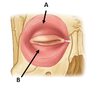

Which muscle is this? What are the parts (A and B)?

Orbicularis oculi (CN VII)

A: Orbital part

B: Palpebral part